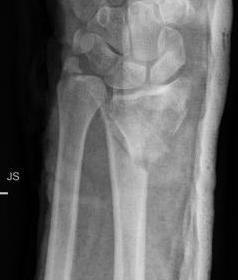

Classification ulna styloid fractures

| Type 1: Tip | Type 2: Base | Type 3: Proximal to styloid |